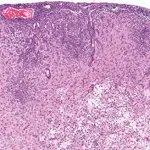

• GME is characterized by a unique angiocentric granulomatous encephalitis consisting of a perivascular accumulation of macrophages often intermixed with lymphocytes and plasma cells. Three major patterns of histologic lesion distribution in the brain and spinal cord have been described for GME:

The disseminated form, in which the most intense lesions occur in the upper cervical spinal cord, brainstem, and midbrain, often with less severe extension involving white matter of the rostral cerebrum (Figure 3).

Figure 3

GME. Disseminated form of GME with an angiocentric expansive infiltration of macrophages sometimes mixed with lymphocytes and a few plasma cells. (_H&E stain, 130×).

A disseminated form with angiocentric expansion forming multiple coalescing mass lesions of similar distribution.

A focal form, in which single discrete mass lesions occur in either the spinal cord, brainstem, midbrain, thalamus, optic nerves, or cerebral hemispheres, without dissemination. It remains contentious whether this form is a neoplastic rather than an immunoproliferative process.